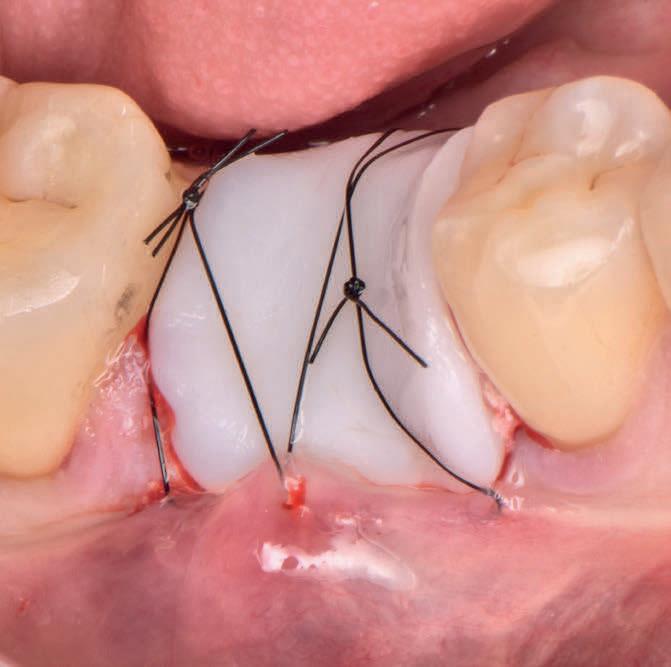

Minimise Complications and Improve Healing Conditions In Mucogingival and Implant Surgery

Leveraging the antibacterial and wound-healing properties of zinc ions, Elemental can be used post-operatively with or without a membrane.

Elemental activates when in contact with boiling water, and the resulting material, which sets rigid and stable, can be quickly and easily moulded and shaped according to the needs of the patient.